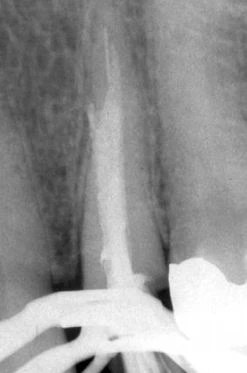

Hình 6. A, Trâm H có đường kính nhỏ xuyên qua chóp của răng nanh hàm trên bị gãy ở đoạn 1/3 cổ ống tủy. B, Mảnh dụng cụ được tháo ra bằng một kìm Masserann, và hình ảnh chi tiết của cơ chế khóa. Lưu ý: trâm nikel-titanium (NiTi) không thể bị uống bằng cách này. Lực khóa của kìm lên dụng cụ nikel-titanium hầu như rất yếu. C, Hoàn tất việc điều trị lại.

Hình 6 cho thấy một trường hợp thất bại trong đó một trâm H cỡ nhỏ bị bỏ lại ở 1/3 cổ ống tủy và kéo dài quá chóp gần 2 mm. Phần còn lại của ống tủy được trám bít bằng gutta percha. Việc lấy mảnh dụng cụ được hoàn thành bởi một kìm IRS sau khi loại bỏ phần gutta percha phía trên bằng đầu siêu âm.